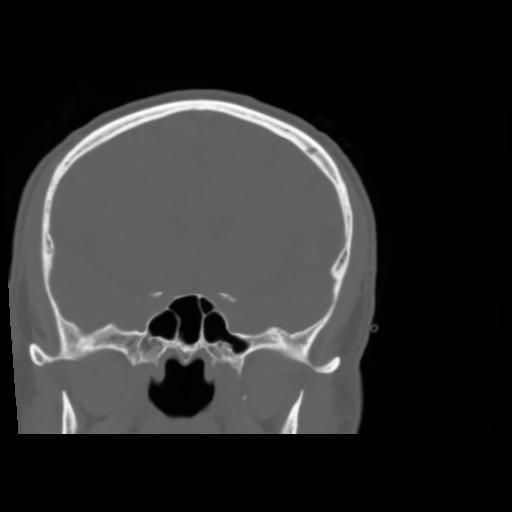

5 CEREBRO,,Coronal,3.000,CEREBRO,Coronal,